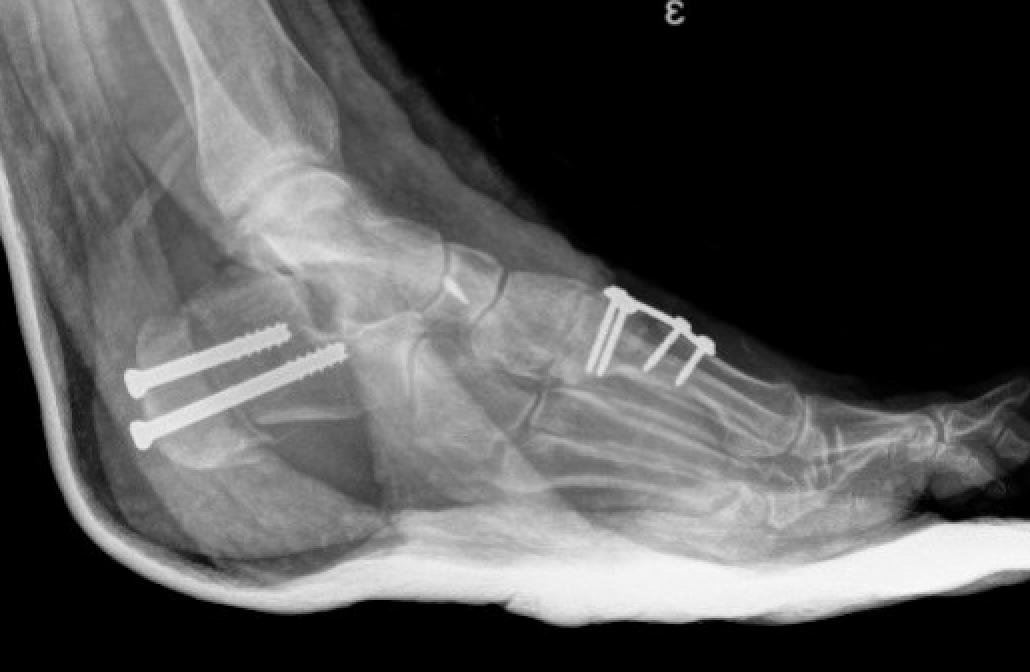

Dwyer lateral closing wedge calcaneal osteotomy

Technique

Lateral approach

- posterior and inferior to peroneal tendons

- resect lateral wedge of bone

- reduce calcaneal ostoeotmy and fix with screws

Lateral displacement calcaneal osteotomy

- curve just behind peroneals

- homann in front of tendoachilles

- homann under calcaneum

Oblique osteotomy behind posterior facet

- 45o

- open with lamina spreader

- split periosteum medially with osteotome

- avoid damage to medial structures

- transfer laterally 1 cm

- screw fixation